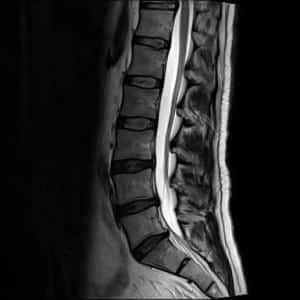

Наиболее эффективным методом диагностики считается магнитно-резонансная томография. С помощью МРТ можно получить высококачественные изображения мягких тканей, определить место локализации и степень развития патологии, а также измерить диаметр сужения межпозвоночного канала.

МРТ противопоказано в период с 1 по 20 неделю беременности. Проведение томографии может изменить температурный режим амниотической жидкости, что может негативно сказаться на здоровье плода. МРТ разрешено проводить в третьем триместре, а на ранних сроках это возможно только при наличии строгих показаний.